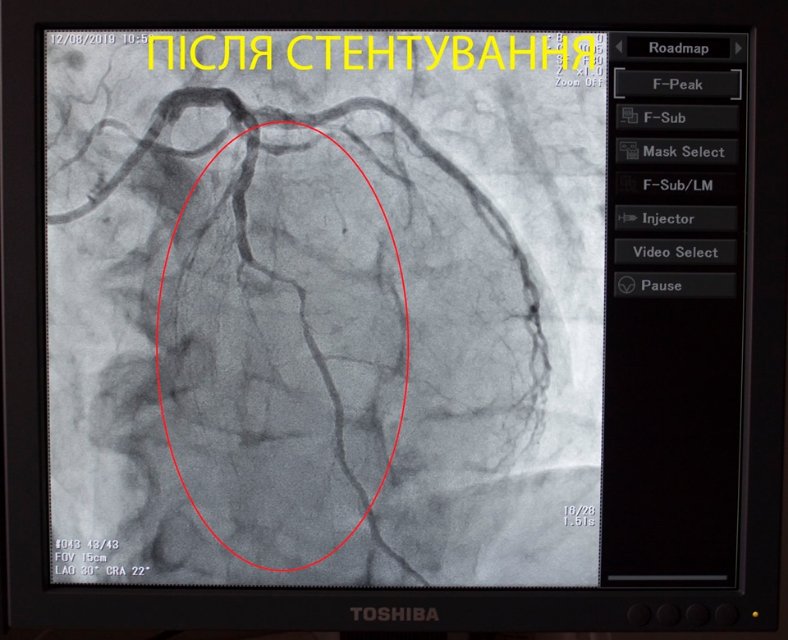

Волинські кардіохірурги Ковельського МТМО провели складну операцію зі стентування коронарної (серцевої) артерії.

"Сьогодні нашими кардіохірургами було виконано чергове стентування коронарної (серцевої) артерії пацієнту з інфарктом міокарда", - йдеться у повідомленні.

Зазначають, інфаркт виникає через припинення кровотоку до серцевого м'яза.

Відтак, стент допомагає розширити судинку та відновити циркуляцію крові.